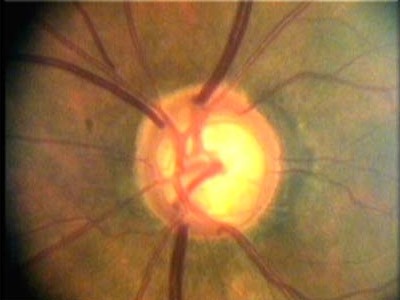

Současné zobrazovací metody glaukomu považujeme za velmi přínosné pro stanovení diagnózy glaukomu a sledování vývoje onemocnění v čase. Těmito metodami sledujeme objektivně projevy glaukomové neuropatie včetně její progrese.